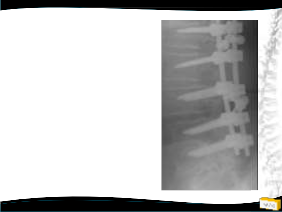

Yapılan Ameliyat

• T12-L5 tp fiksasyon

• L4 laminektomi ile L3-L4 ve L4-L5 mesafelerinin dekompresyonu

• Posterolateral grefleme

• 3 yıllık takipte sorunsuz